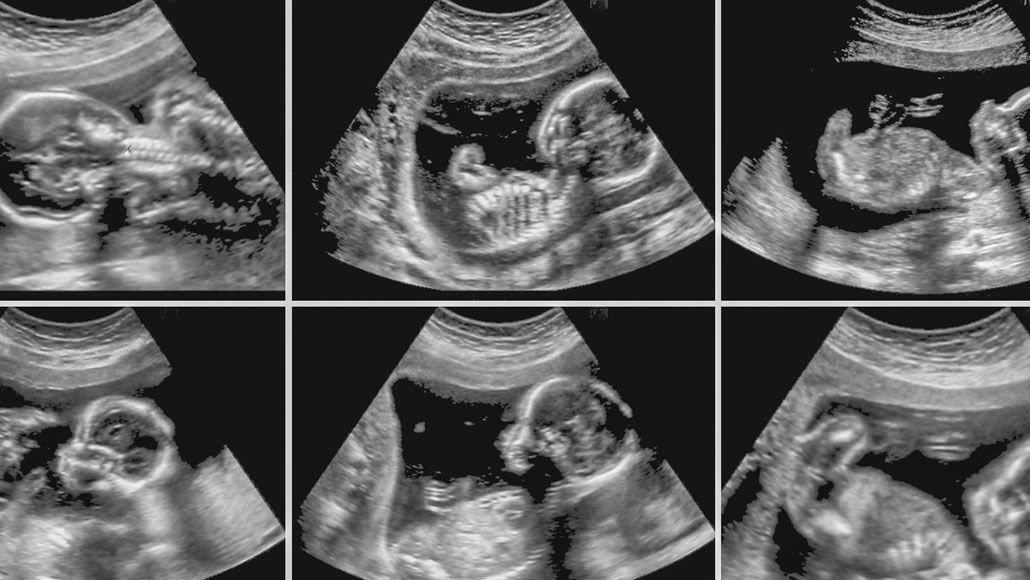

Jovannig/iStock /Getty Images Plus